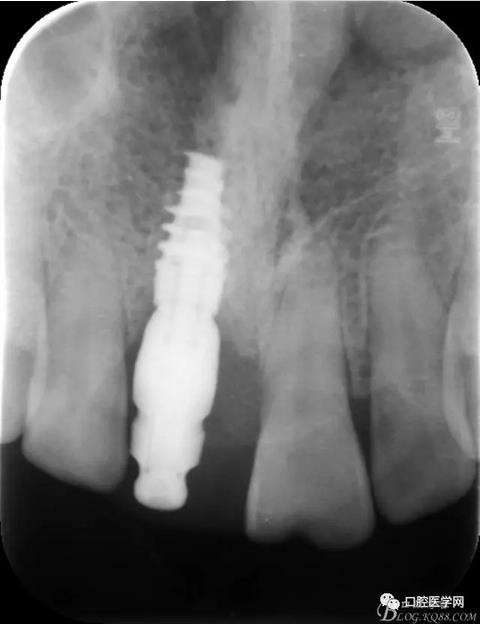

X 光 示:11 根折,根尖無明顯異常

圖1 術(shù)前X光片